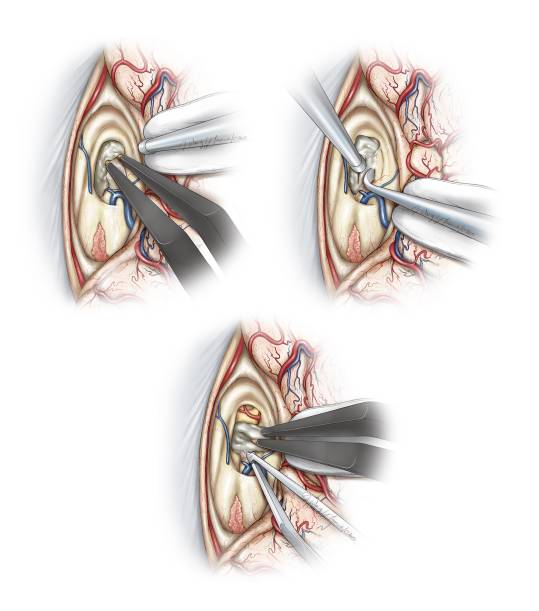

图10. 将覆盖在Monro孔和静脉角表面的脉络丛前方切断,然后轻柔的钝性分离和电凝。肿瘤通常会扩大室间孔,但是无法提供足以完整切除肿瘤的手术通道(Redrawn from Tew,van Loveren, Keller*)。

图11. 将隔静脉在临近室间孔处汇入丘纹静脉时分离并电凝,然后切断(上图)。下图提供了关于右侧脑室及相关解剖的术中照片。

图12.分离切断隔前静脉后,在丘纹静脉后方分离脉络裂可获得肿瘤和三脑室前中部的良好显露。在隔前静脉被电凝然后锐性切断后,向内侧轻柔地推移穹隆。通常在室间孔后缘和同侧丘纹静脉前缘之间有少许室管膜,可以采用显微剥离子切开室管膜之后用双极电凝颞轻轻的扩大(上图)。这一操作能明显扩大室间孔,有利于增加经三脑室的显露视野(下图为术中照片)。第三脑室左侧壁被标记(*)。

沿同侧大脑内静脉内壁分离并向后延伸,进一步扩大进入三脑室的手术通道,直至显露双侧大脑内静脉,该空间足以显露病变的后极。